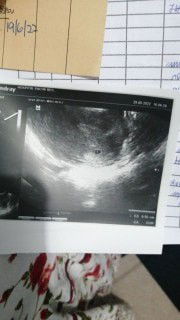

Assalamualaikum harap ramai yang sudi respon. Last scan 8week tapi saiz kantung 6 week+ x nmpk heartbeat lagi just nmpk biji kacng kecik dalam kantung. 1 Mcm gini bleeding atau spotting? 2. Hari nie dah 6 hari keluar mcm nie dari first keluar lagi saya dh pergi Kecemasan. Dr maklumkan sy ada luka pangkal rahim. Tu yg menyebab kan keluar. Dr just suruh badrest. Tapi saya risauu Adakah patut sy pergi lagi Kecemasan lagi? Atau tunggu 3 hari lagi ahad app Dr pakar. 3. Siapa kes mcm saya apa yang awak buat kandungan dpt bertahan atau sebaliknya. 4.luka pangkal rahim sbb keputihan sy rse sy tapi dah buat pap smear sblm ngandung tapi Dr kata normal. Tolong saya. #seriusnanya #pleasehelp

Sy ex ep bulan 12/2021 skrg Alhamdulillah mengandung lagi. Dapat tahu sahaja saya buat betahcg Bacaan 1 :322 Bacaan 2 :826 Normal ke? Pernh dengar kena naik 2 kali ganda. Nie scan time 4 week. Tapi Dr kata maybe baru 3 week. Sbb sgt2 kecik ada ke yang scan 0.55 cm. Ada tak yang sama mcm saya doakan ya kandungan kali ini sihat dan dalam rahim dengan sebaik2nya #firstbaby #firstmom